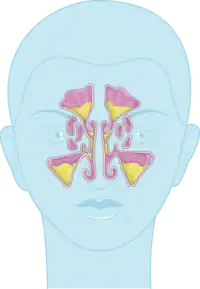

The four paired paranasal sinuses are the frontal, ethmoidal, maxillary, and sphenoidal sinuses. The ethmoidal sinuses are further subdivided into anterior and posterior ethmoid sinuses, the division of which is defined as the basal lamella of the middle nasal concha. In addition to the severity of disease, discussed below, sinusitis can be classified by the sinus cavity it affects:

- Maxillary – can cause pain or pressure in the maxillary (cheek) area (e.g., toothache,[18] or headache) (J01.0/J32.0)

- Frontal – can cause pain or pressure in the frontal sinus cavity (located above the eyes), headache, particularly in the forehead (J01.1/J32.1)

- Ethmoidal – can cause pain or pressure pain between/behind the eyes, the sides of the upper part of the nose (the medial canthi), and headaches (J01.2/J32.2)[24]

- Sphenoidal – can cause pain or pressure behind the eyes, but is often felt in the top of the head, over the mastoid processes, or the back of the head.[24]